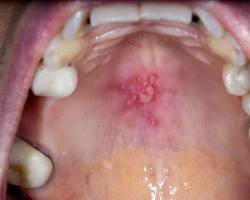

- Cold Sores:

Cold sore on the roof of the mouth